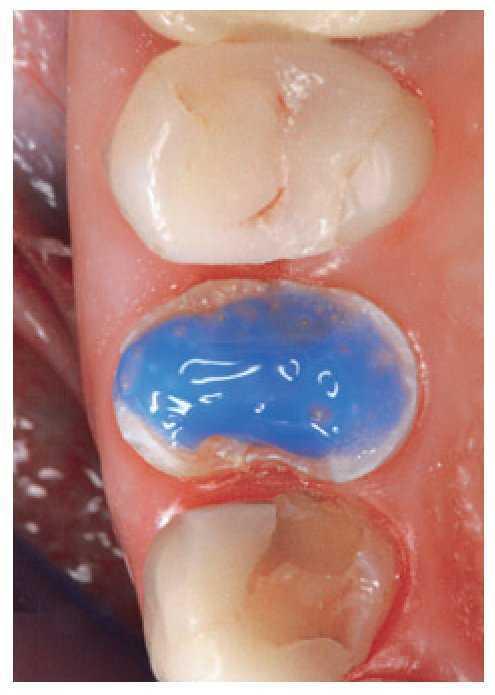

Para la técnica adhesiva es necesario crear un aislamiento absoluto con un dique de goma. No obstante, la paciente presentaba una infección de vías respiratorias altas y sólo podía respirar por la boca. Cuando intentamos colocar el dique de goma cayó presa del pánico, De modo que colocamos un rollito de algodón en el vestíbulo y cubrimos el suelo de la boca con una gasa suelta con el fin de aislar la zona de los premolares superiores lo mejor posible (fig. 9).

Figura 9. Aislamiento del campo con una gasa.